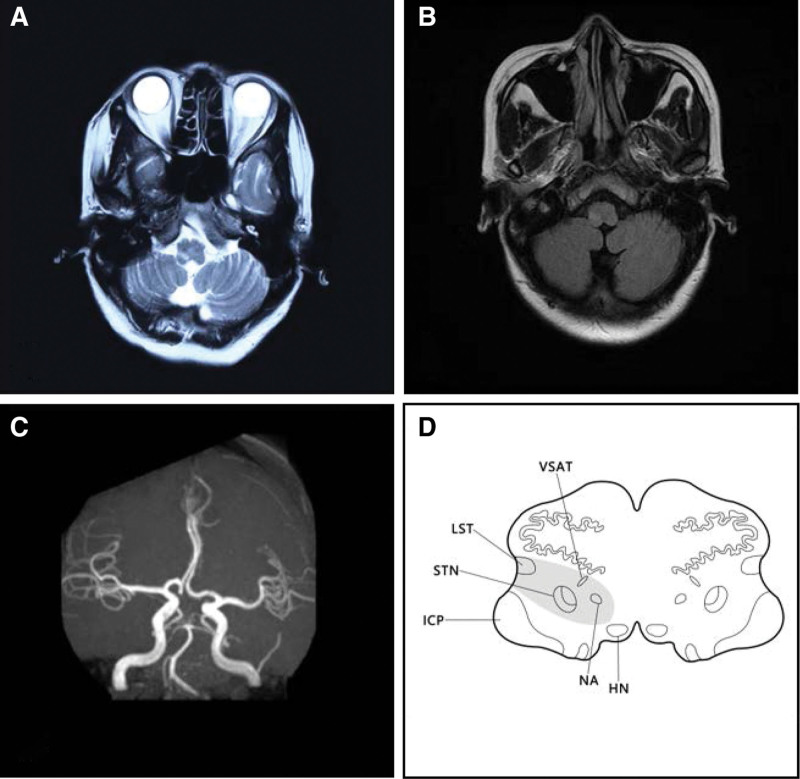

T2-weighted MRI images on December 17, 2020 demonstrated a high-signal intensity lesion in the right MO which indicating a banded infarction site (Fig. 1A). Fluid-attenuated inversion recovery images of brain MRI on T2 sequences on December 22, 2020 showed slight high-signal intensity in the infarcted site (Fig. 1B). What’s more, the magnetic resonance angiography on December 22, 2020 demonstrated that the left dominant vertebral artery which tortuously to the right with no abnormality was observed in the remaining cerebrovascular vessels (Fig. 1C). The patient was diagnosed with MO infarction, Avellis syndrome, Horner syndrome, dysphagia, and hemiparesthesia.

T2-weighted MRI images on December 17, 2020 demonstrated a high-signal lesion in the right medulla oblongata which indicating a banded infarction site (A); FLAIR images of brain MRI on T2 sequences on December 22, 2020 showed slight high-signal in the infarcted site (B); MRA on December 22, 2020 demonstrated that the left dominant vertebral artery which tortuously to the right with no abnormality was observed in the remaining cerebrovascular vessels (C); the simulated diagram of the patient’s lesioned area shows the affected NA, LST, VSAT, and STN. FLAIR = fluid-attenuated inversion recovery, HN = hypoglossal nucleus, ICP = inferior cerebellar peduncle, LST = lateral spinothalamic tract, MRA = magnetic resonance angiography, MRI = magnetic resonance imaging, NA = nucleus ambiguous, STN = spinal trigeminal nucleus, VSAT = ventral trigeminothalamic tract (ventral secondary ascending tract of trigeminal nucleus).

The clinical manifestations of Avellis syndrome may vary depend on the lesion size and the involved nuclei as well as fibrous bundles. The nucleus ambiguus and the lateral spinothalamic tract are the most affected targets of Avellis syndrome in the case of MO infarction. However, in the case of MO infarction, the surrounding structures such as nucleus tractus spinalis nervi trigemini, nucleus of hypoglossal nerve, nucleus of accessory nerve, nucleus of the solitary tract, nucleus nervi vestibularis, trigeminal thalamic tract, and sympathetic fibers may be affected thus generate additional symptoms.[7] Hoarseness, dysphagia, diminished sensation (light touch, pain, and temperature) of the contralateral face, trunk, and limbs are the most frequently reported clinical manifestations of Avellis syndrome. Hoarseness was reported in 9 cases of Avellis syndrome among the representative literatures[3,5,7,8]; dysphagia was reported in 6 cases; decreased sensation of the contralateral limbs or trunk was reported in 8 cases; diminished sensation of the contralateral face was reported in 4 cases; ipsilateral Horner syndrome and contralateral hemiplegia were mentioned in 4 cases and 1 case, respectively; ipsilateral peripheral facial paralysis which was due to the infarction of the pons was also mentioned in 1 case (see Table 1). In the current report, the patient presented with ipsilateral palatopharyngeal muscle palsy which could be explained by the affected nucleus ambiguous, glossopharyngeal nerve and the vagus; the occurrence of the diminished sensation of pain and temperature in the contralateral face may probably resulted from the damage to the ventral trigeminothalamic tract; the affected lateral spinothalamic tract may probably cause the sensation (pain and temperature) of the contralateral limbs and trunk to subside (Fig. 1D). In addition to the clinical manifestations, the cerebral MRI plays a significant role in the diagnosis of Avellis syndrome. The brain MRI images of this patient are consistent with what Takizawa, S, and Y Shinohara previously reported in a typical Avellis syndrome case which manifests as strip-like lesions that extending from the medial and lateral surfaces of the upper MO into the dorsimedial parenchyma which is usually demonstrated as decreased signal intensity on T1 sequences while increased signal intensity on T2 sequences.[9] In general, the patient is affected by Avellis syndrome regarding the typical clinical manifestations as well as the cerebral MRI images.